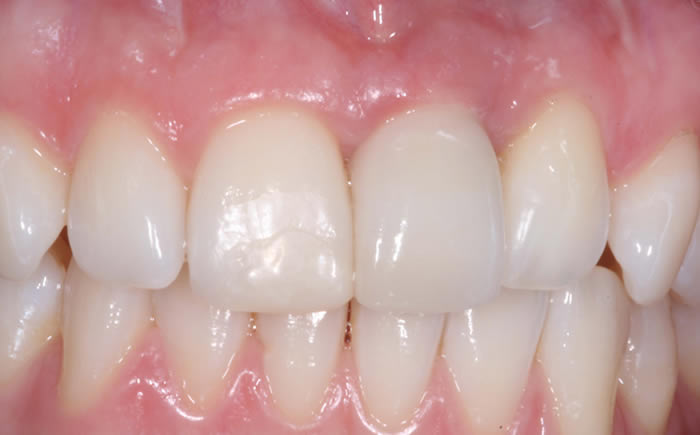

Front teeth replaced by dental implants

Case One (5 images)

Dental implants used to replace two upper front teeth

Case Two (4 images)

Missing upper front tooth replaced by dental implant and crown